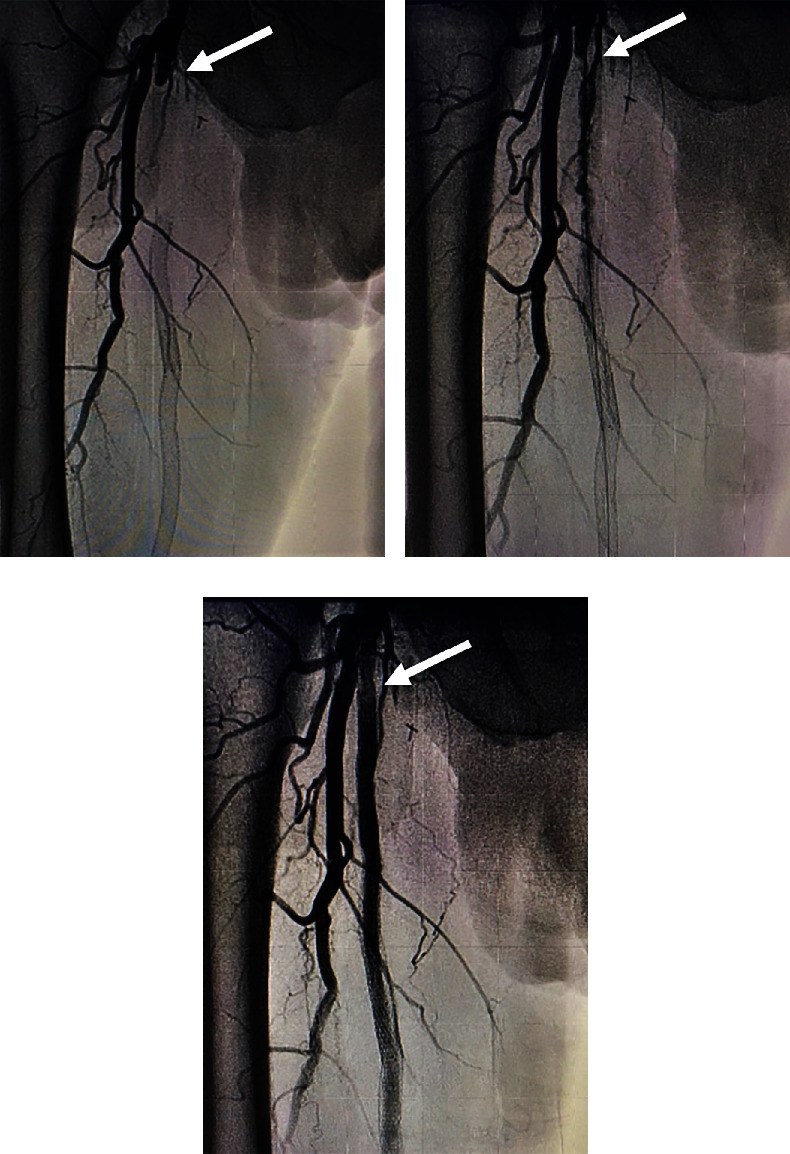

Peripheral arterial disease (PAD) affects more than 230 million adults worldwide. Revascularization via angioplasty is a common method to manage stenosis in the superficial femoral artery (SFA). In-stent restenosis, however, is a common complication in endovascular interventions, especially in the SFA. Here, we present a case that involves recanalization of the SFA in a patient with a previously occluded stent and failed surgical revascularization. This patient initially presented with an occluded SFA which was stented. Four years later, the stent was reoccluded and surgical endarterectomy of the artery was performed with partial removal of the stent. Ten years later, the SFA is again occluded. Recanalization of the SFA using laser atherectomy and restenting of the occluded stent with GORE VIABAHN endoprosthesis was performed successfully. The combination of such methods is a suitable way to manage chronic lesions and minimize restenosis in patients with PAD.

Abstract Image